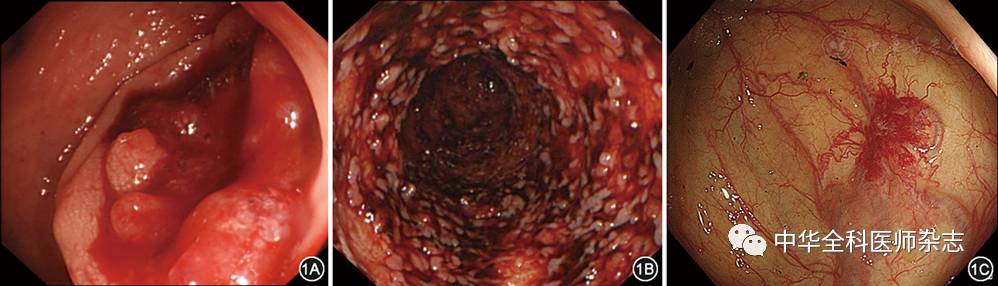

结肠镜可直视观察黏膜病变并取活检,是诊断LGIB病因的最佳方法(图1)。文献报告89%~97%的LGIB患者可经急诊结肠镜检查而获确诊[10]。在部分出血病例,结肠镜还可通过金属夹、氩离子凝固术(argon plasma coagulation)、黏膜下注射、喷洒止血药物、内镜下套扎、外置内镜金属夹(over the scope clip)等技术在内镜下止血。基于这些优势,目前结肠镜已成为急性LGIB的首选诊疗手段[4,5]

图1 通过结肠镜确诊的急性下消化道出血。1A:结肠癌,1B:溃疡性结肠炎,1C:结肠血管畸形